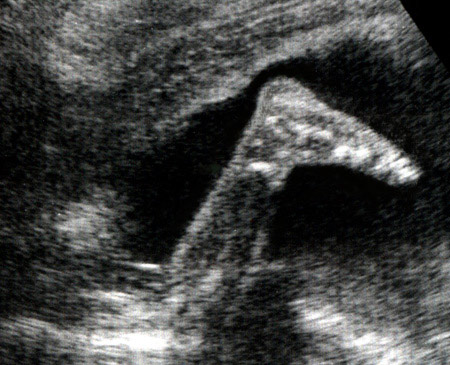

Pied fœtal à 24 semaines d'aménorrhée

Vue de profil